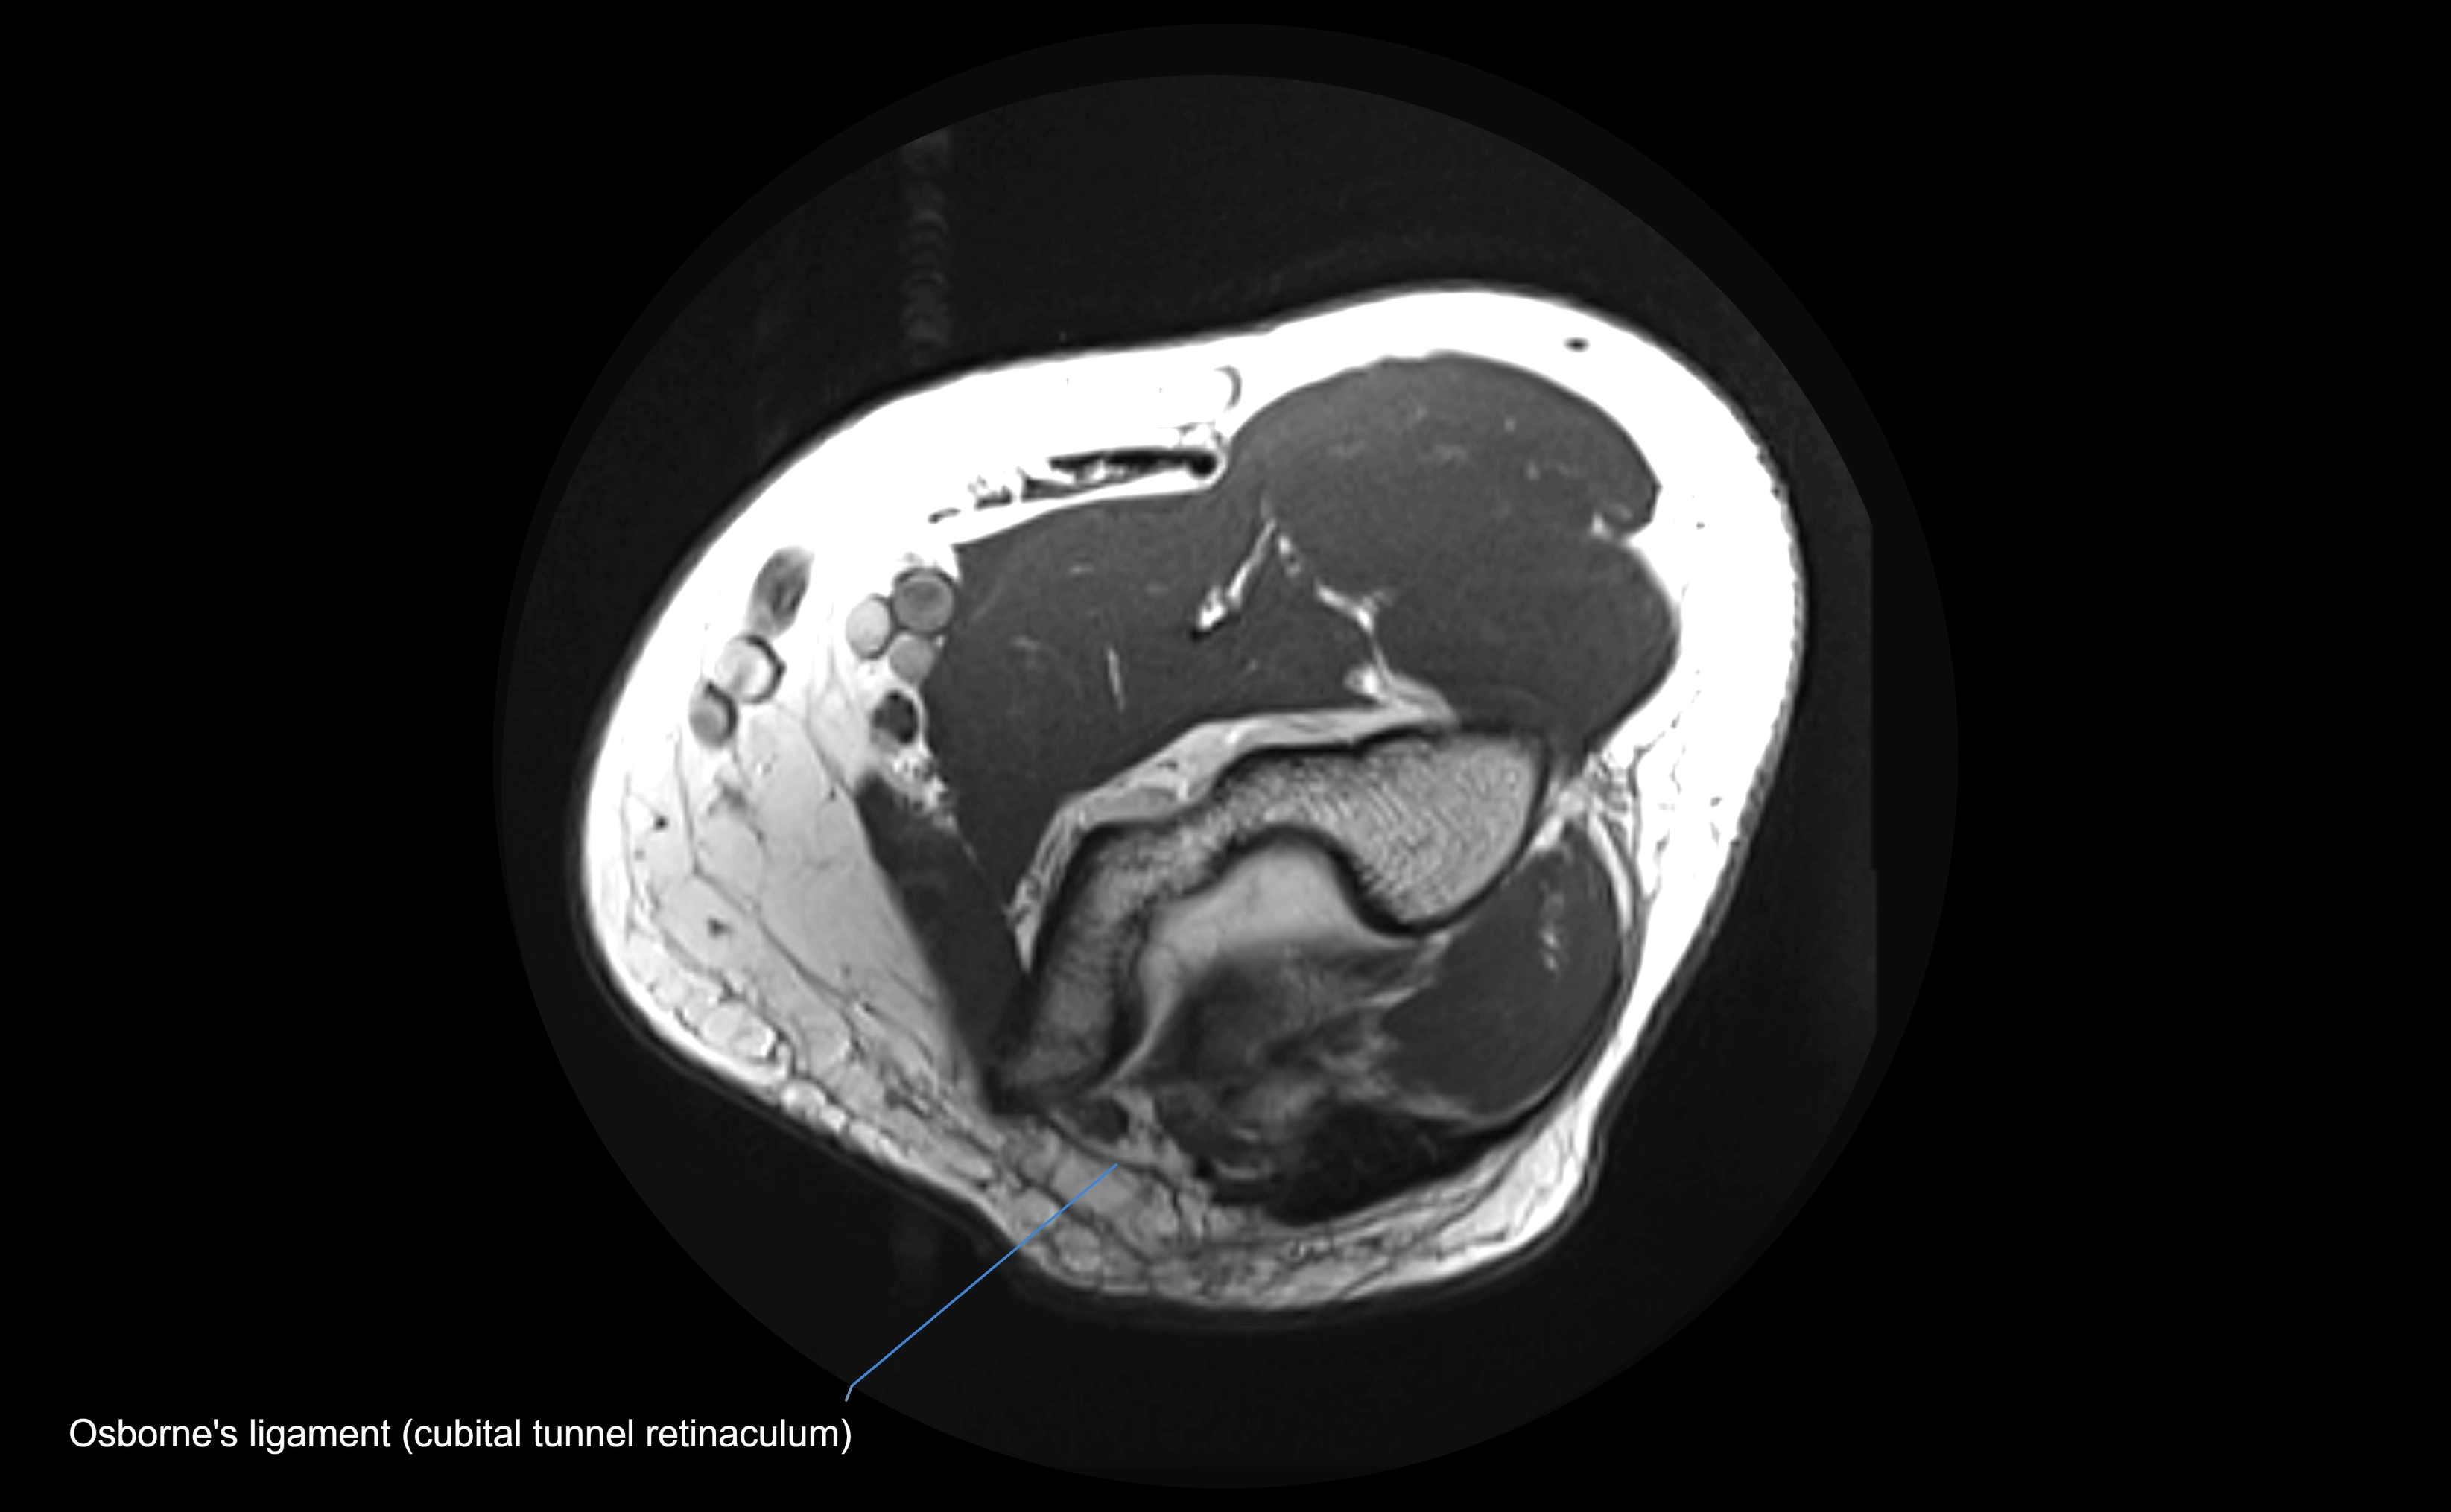

MRI Appearance

T1-weighted images:

• Ligament: low signal intensity (dark), appearing as a continuous band around the radial head.

• Adjacent fat and marrow: bright, creating contrast with the ligament.

• Thickening or disruption indicates injury or fibrosis.

• Joint capsule and synovium seen as thin low-signal lines contiguous with ligament margins.

MRI Arthrogram Appearance

• Contrast outlines the proximal radioulnar joint and radial head recess.

• Normal ligament appears as a dark ring surrounding the radial head, containing the injected contrast within the joint cavity.

• Partial tear: contrast extends along the ligament or beneath its fibers.

• Complete tear or subluxation: contrast extravasates around the radial head or ulna, indicating discontinuity.

• Detects capsular defects, instability, or synovial invagination with high sensitivity.

MRI images

image